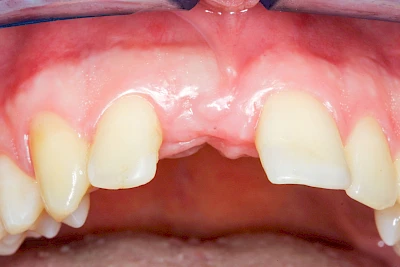

Fehlen einzelne Zähne und die Nachbarzähne sind unbeschadet oder gut zahnärztlich versorgt, werden immer häufiger Implantate gewählt, um die Lücken zu schließen. Auch bei größeren oder verteilten Lücken, wenn keine herausnehmbare Prothese gewünscht ist, werden Implantate für Kronen- bzw. Brückenversorgungen gesetzt. In Einzelfällen entscheiden sich sogar zahnlose Patienten für eine festsitzende Versorgung auf Implantaten.

Varianten zur Verankerung von festsitzendem Zahnersatz auf Implantaten